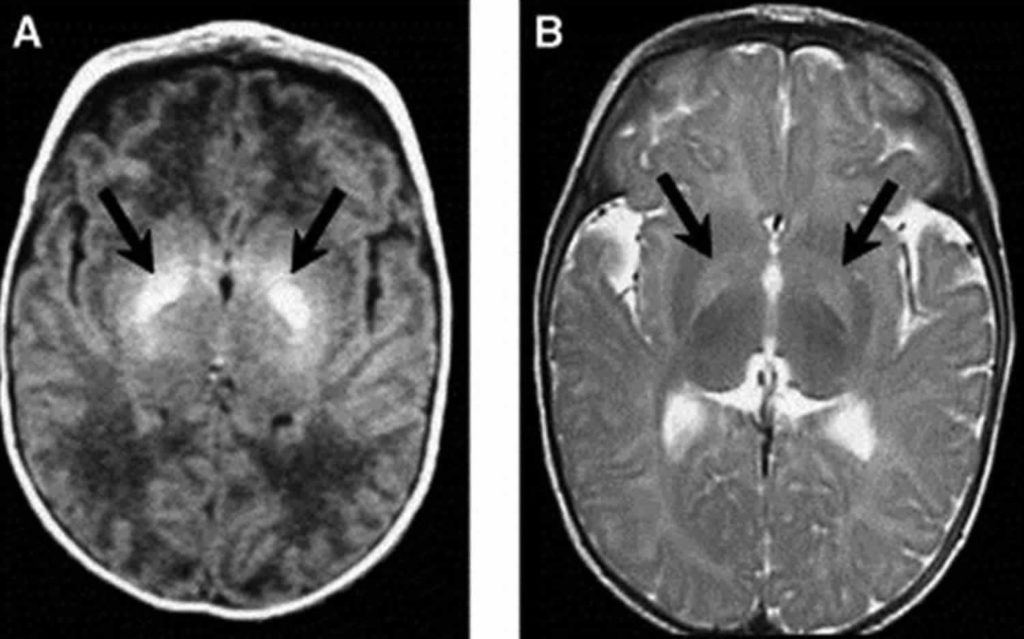

Ultimate Radiology Bilateral basal ganglia T1 hyperintensity Basal Ganglia Kernicterus  It gets deposited in the brain tissue, mainly the basal ganglia. And cranial nerve nuclei, such as the oculomotor, vestibular, and. Kernicterus is brain damage caused by unconjugated bilirubin deposition in basal ganglia and brain stem nuclei. Failure to initiate appropriate therapy such as phototherapy or exchange transfusion may result in bilirubin deposition causing. This activity reviews the evaluation and. Basal Ganglia Kernicterus.